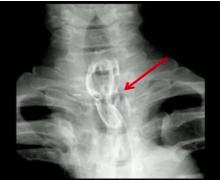

An intrathoracic esophago-gastric anastomosis has the potential to reduce morbidity and mortality in patients undergoing minimally invasive esophagectomy (MIE) for cancer. Esophageal squamous cell carcinoma (SCC) has a high incidence of early lymphatic spread and is usually located in the midthorax, in comparison to esophageal adenocarcinoma. Consequently, the anastomosis should be made high in the thorax or in the neck. A high intrathoracic anastomosis using thoracoscopy, if applicable, is an attractive alternative procedure to a cervical anastomosis, to reduce the incidence of complications such as vocal cord palsy and anastomotic leak. The authors present their experiences and outcomes with patients with esophageal squamous cell carcinoma treated by high intrathoracic circular anastomosis using a thoracoscopic technique.